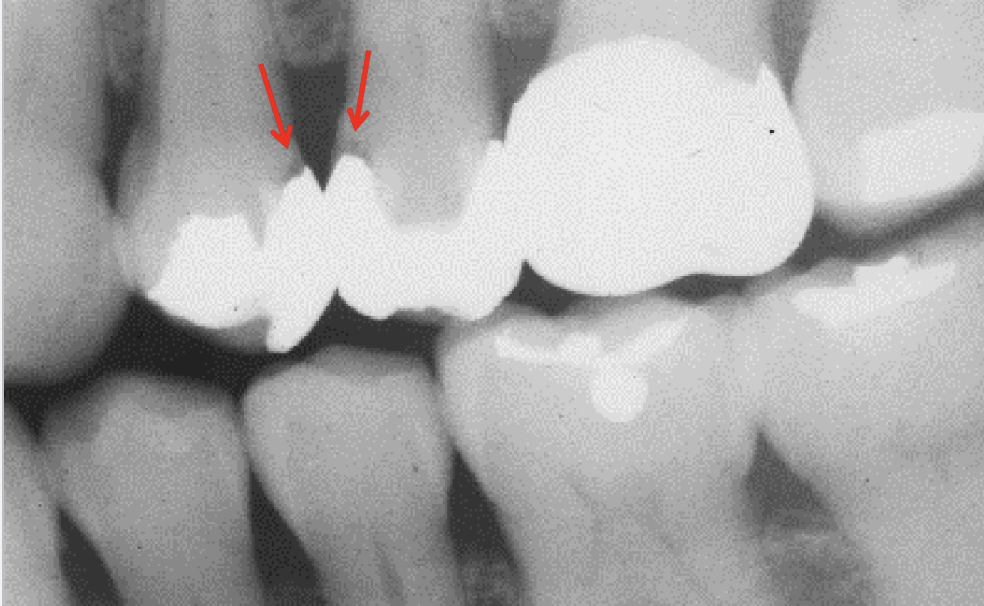

Q

Classify the caries

A

recurrent caries (RC)